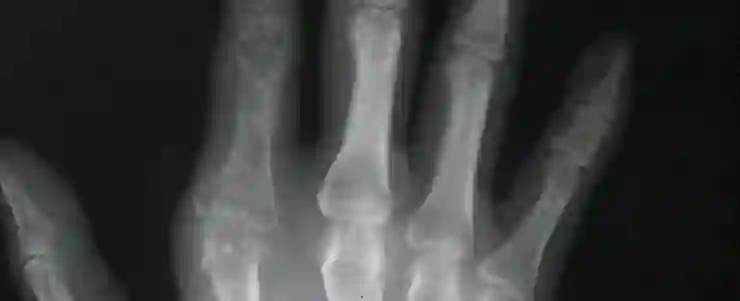

一、450名骨科医生不敌AI阅片

5月11日上午在中国医师协会骨科医师分会年会上, 450名骨科医生对战骨科AI智能阅片,AI得90分,略高于医生综合得分。